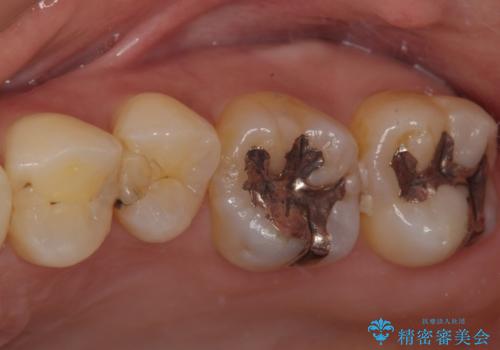

歯に穴があいてフロスが引っかかる セラミックインレー修復

- 当院で矯正終了後、歯に穴が開いてフロスが引っかかるとのことでセラミックで修復することになった患者様です。

虫歯がないか確認し、セラミックインレーにて修復することになりました。